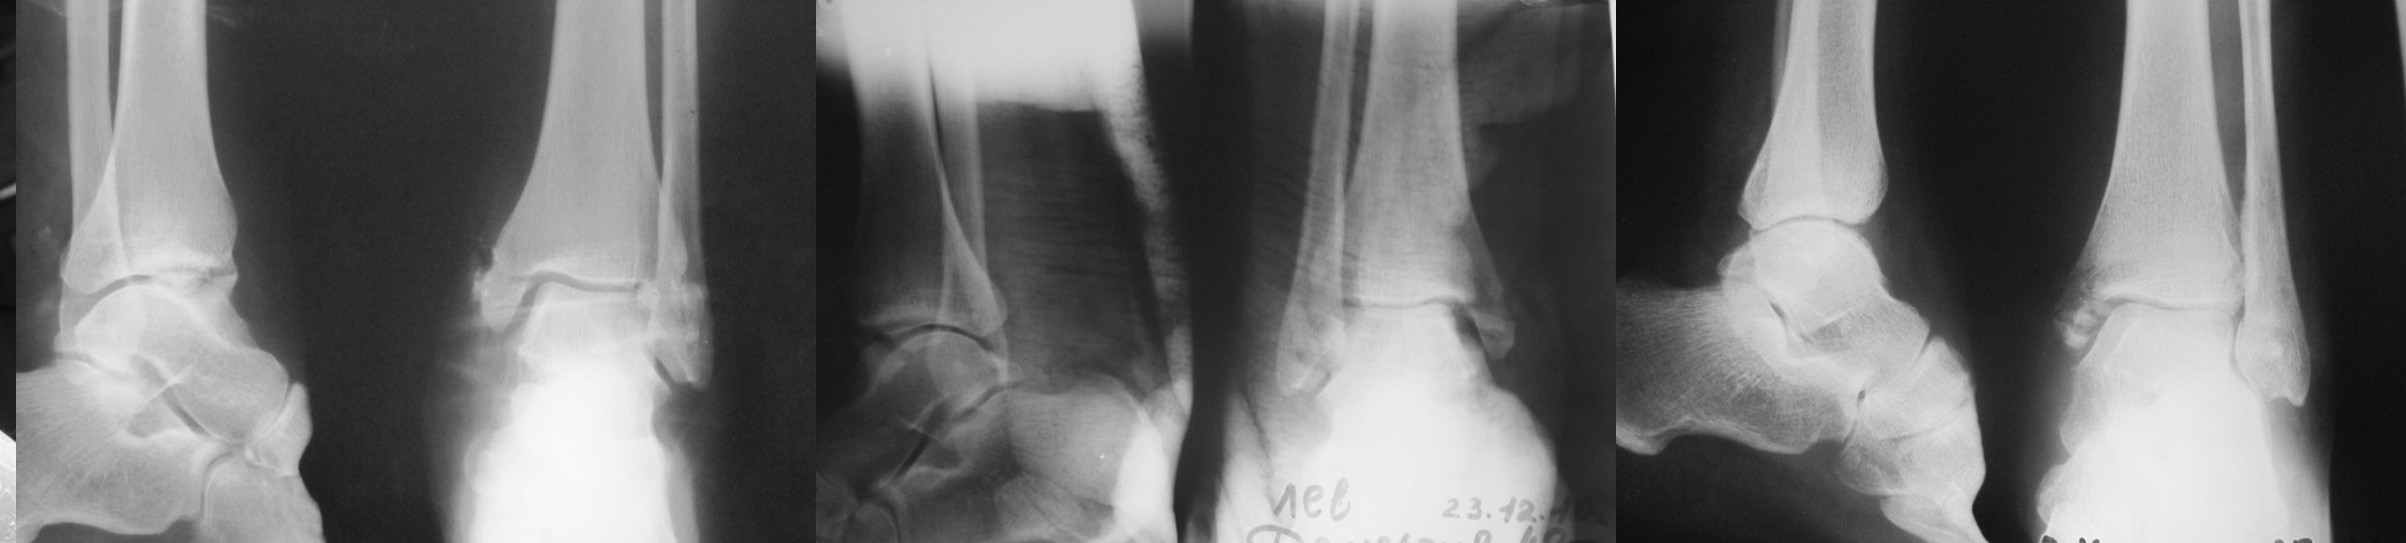

Уважаемые коллеги! Помогите определиться с тактикой лечения больной 50 лет! Травма в результате ДТП 1 января 2011г. открытый многооскольчатый перелом медиальной лодыжки левого голеностопного сустава со смещением. При поступлении в области медиальной лодыжки поперечная рана 5,0х1,0 см. сильно загрязнена, была выполнена ПХО. 05.01.2011г. сняты все швы по поводу нагноения раны, выполнена некрэктомия нежизнеспособных краев раны. На сегодня голеностопный сустав незначительно отечен, слегка болезнен при пальпации в области медиальной лодыжки. Температура тела нормальная, боли практически нет. Кровь спокойная. В области медиальной лодыжки имеется ранка округлой формы до 0,3 см., со скудным гнойным отделяемым (следы на салфетке после перевязки 1 раз в 2 дня). Посев из раны выполнить невозможно. На последних контрольных рентгенограммах признаки остеомиелита медиальной лодыжки? Помогите определиться с тактикой лечения: оперативное? Консервативное? С уважением Александр Белоконь!

4 недели после травмы - это еще пока открытый срастающийся инфицированный перелом, а не остеомиелит. Что касается рентгенограмм - в таком разрешении трудно оценить структуру кости.

Уважаемые коллеги! Прошу прощения за собственную невнимательность. У больной травма не 1 января 2011г., а 1 декабря 2010г., т.е. уже 2 месяца.

Прилагаю данные фистулогрфии. Основной вопрос, все же, лечить консервативно или оперативно? Если оперативно, то какой объем? А что если прийдеться резецировать всю медиальную лодыжку!?